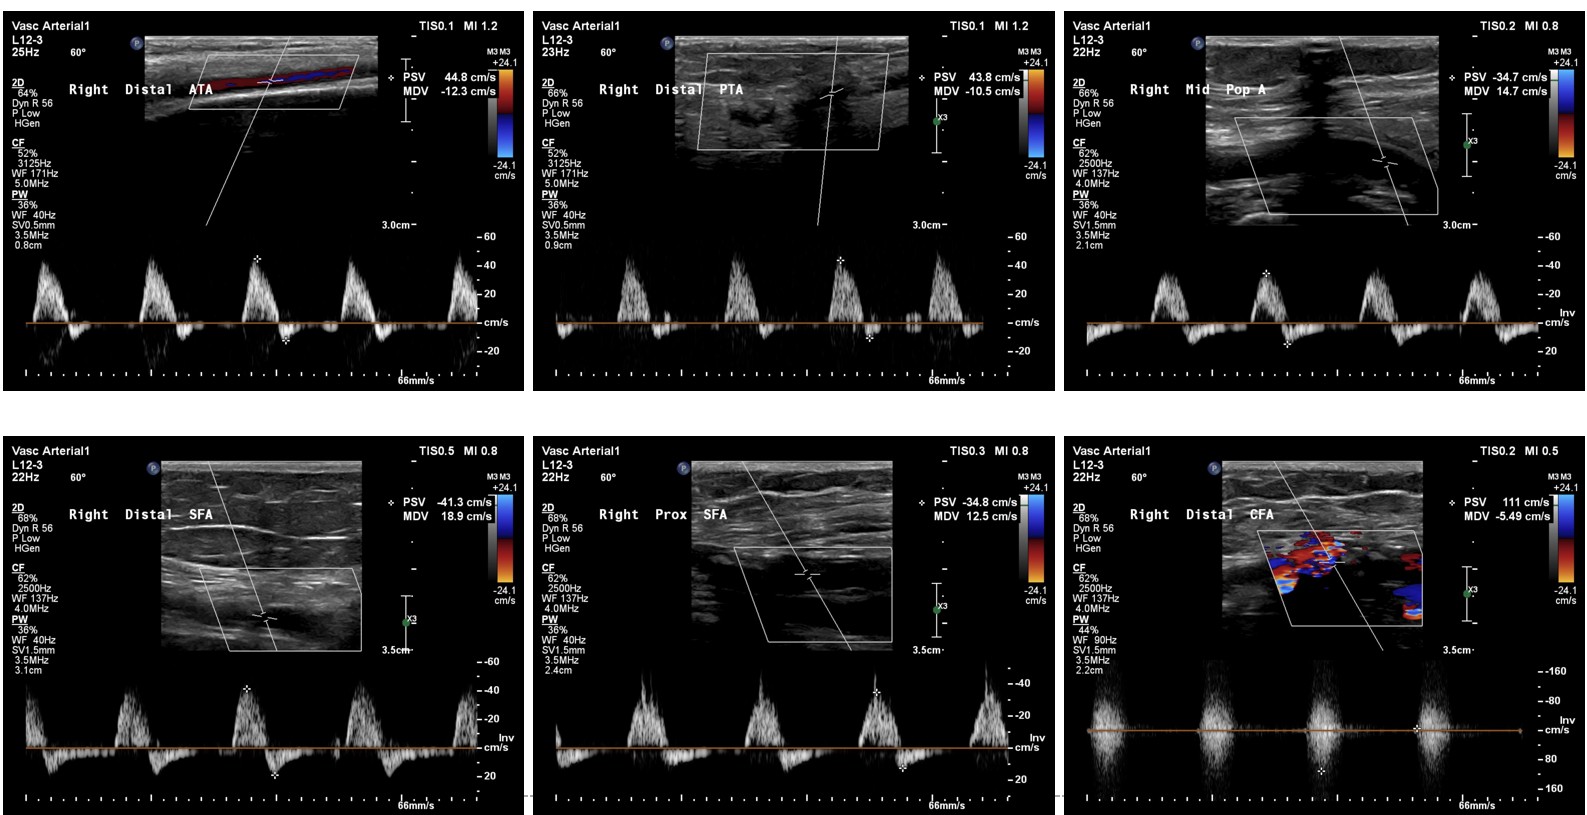

Relevant Test Results Prior to Catheterization

Ankle–brachial index was reduced on the right (0.77) and borderline on the left (0.90), suggesting peripheral arterial disease. CAVI values were within normal range, indicating preserved arterial elasticity. Duplex ultrasound revealed monophasic flow and reduced velocity at the right superficial femoral artery with preserved distal runoff, consistent with a hemodynamically significant proximal obstruction.